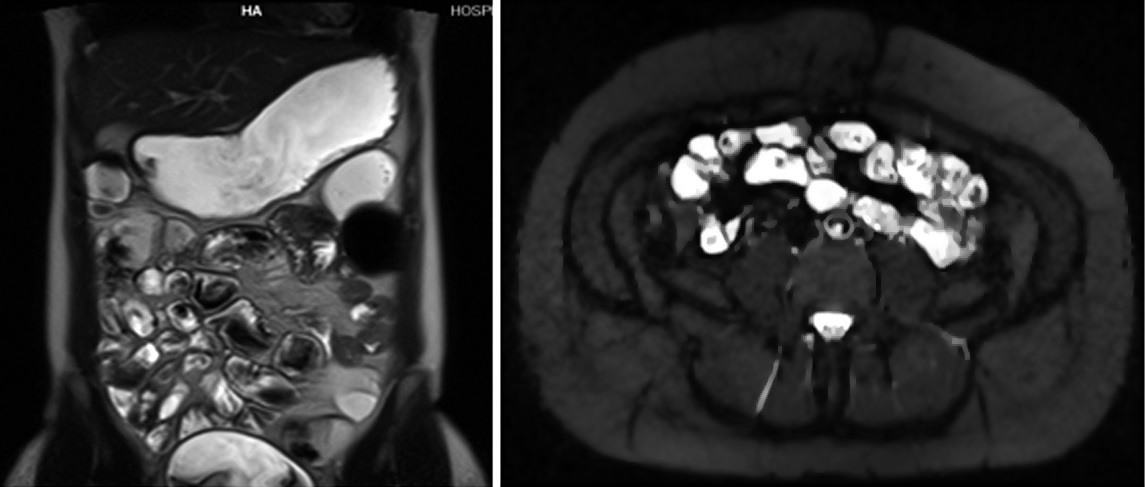

Figura 7

Misma paciente de la figura 6

a y b) Secuencia T2 axial con saturación grasa.

Se observa un grupo de asas en fosa ilíaca derecha de

paredes engrosadas en

forma concéntrica y con edema submucoso (flecha).

c y d) Secuencia de

difusión con valor b 800. E: Mapa de ADC. Se observa

intensa restricción a la

difusión del agua de las asas afectadas. En esta

paciente en quien no se pudo

realizar gadolinio debido a las semanas de gestación se

muestra la importancia

de la difusión en la valoración de actividad

inflamatoria.